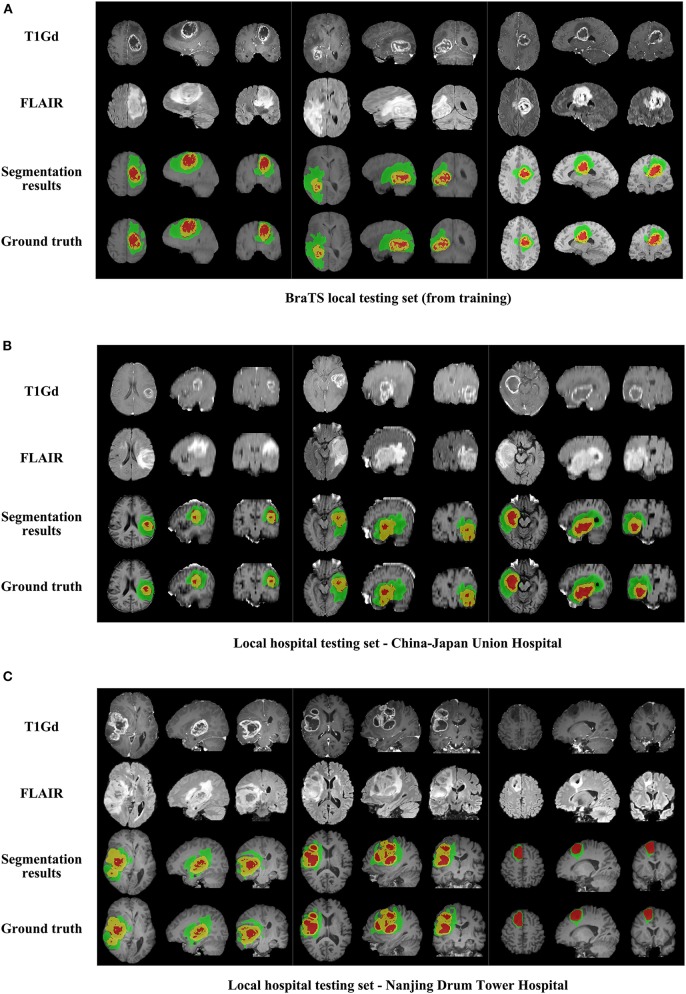

We use 20 percent of all data as our local testing set, which includes 42 HGG patients and 15 LGG patients. Representative segmentation results are shown in Figure 4A. The green shows the edema, the red shows the tumor necrosis, and the yellow shows the enhancing tumor. In order to evaluate the preliminary experimental results, we calculate the average Dice scores, sensitivity, and specificity for whole tumor, tumor core, and enhancing tumor, respectively. The results are shown in Table 3. The segmentation of whole tumor achieves best result with average Dice score of 0.8505.

Figure 4.

The comparison of segmentation results and ground truth on representative cases from local testing set and two clinical testing sets. (A) The segmentation results and ground truth from local testing set. (B) The segmentation results and ground truth from clinical testing set of China-Japan Union Hospital of Jilin University. (C) The segmentation results and ground truth from clinical testing set of Affiliated Drum Tower Hospital of Nanjing University Medical School.

Segmentation Results on Clinical Testing Sets of 56 Subjects

Representative segmentation results on two local hospital testing sets are shown in Figures 4B,C. The average Dice scores for whole tumor, tumor core and enhancing tumor in two data sets are calculated, respectively. The details are shown in Table 7. Overall, the images from China-Japan Union Hospital of Jilin University which are acquired using 2D MRI sequences achieve better segmentation results with Dice scores of 0.8635, 0.8036, and 0.7217 for whole tumor, tumor core, and enhancing tumor, respectively. On the other hand, the images from Affiliated Drum Tower Hospital of Nanjing University Medical School which are acquired using 3D MRI sequences achieve poor Dice score of 0.6786 for tumor core.